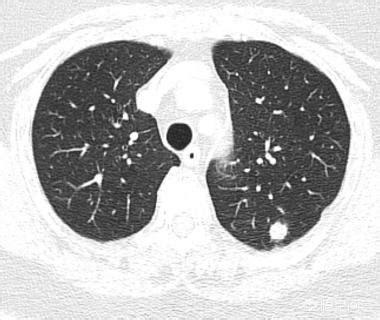

所谓肺小结节,是指直径小于1cm的肺结节,肺结节的大小和肺癌的可能性是正相关的。此回答,我们讨论小结节。

2、有的肺小结节,一开始不是癌,而是不典型腺瘤样增生等,慢慢演变成浸润腺癌,这种多见于磨玻璃结节。

3、有的肺小结节,是良性的,不会演变成肺癌。

比如,肺内淋巴结,可表现为肺内小结节,甚至可以慢慢长大,但这个是良性的,不会恶变。有的磨玻璃结节,随访复查后消失,说明是炎症。还有的结节是结核,其他炎症,或者良性的肿瘤。

当发现了肺结节,要根据临床情况,CT表现等等综合分析,越小的结节,越难以定性,因此有时候才需要随访观察。